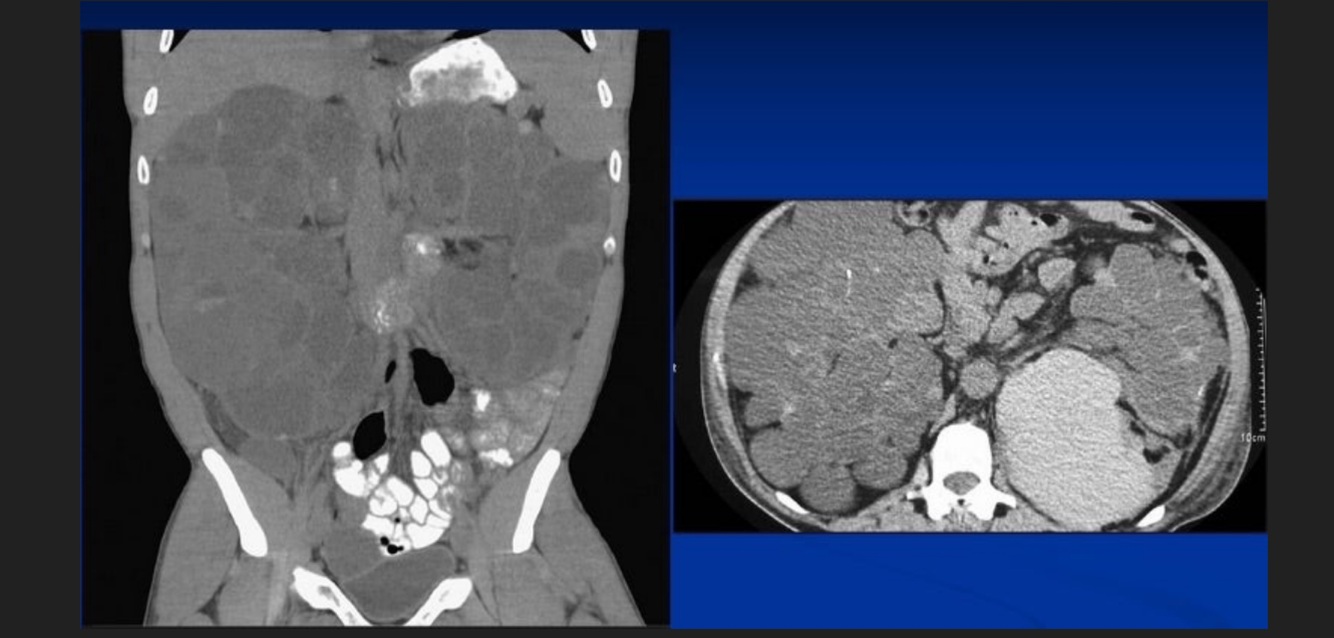

5

Q

IRC secundaria a:

A

Riñones poliquisticos

How well did you know this?